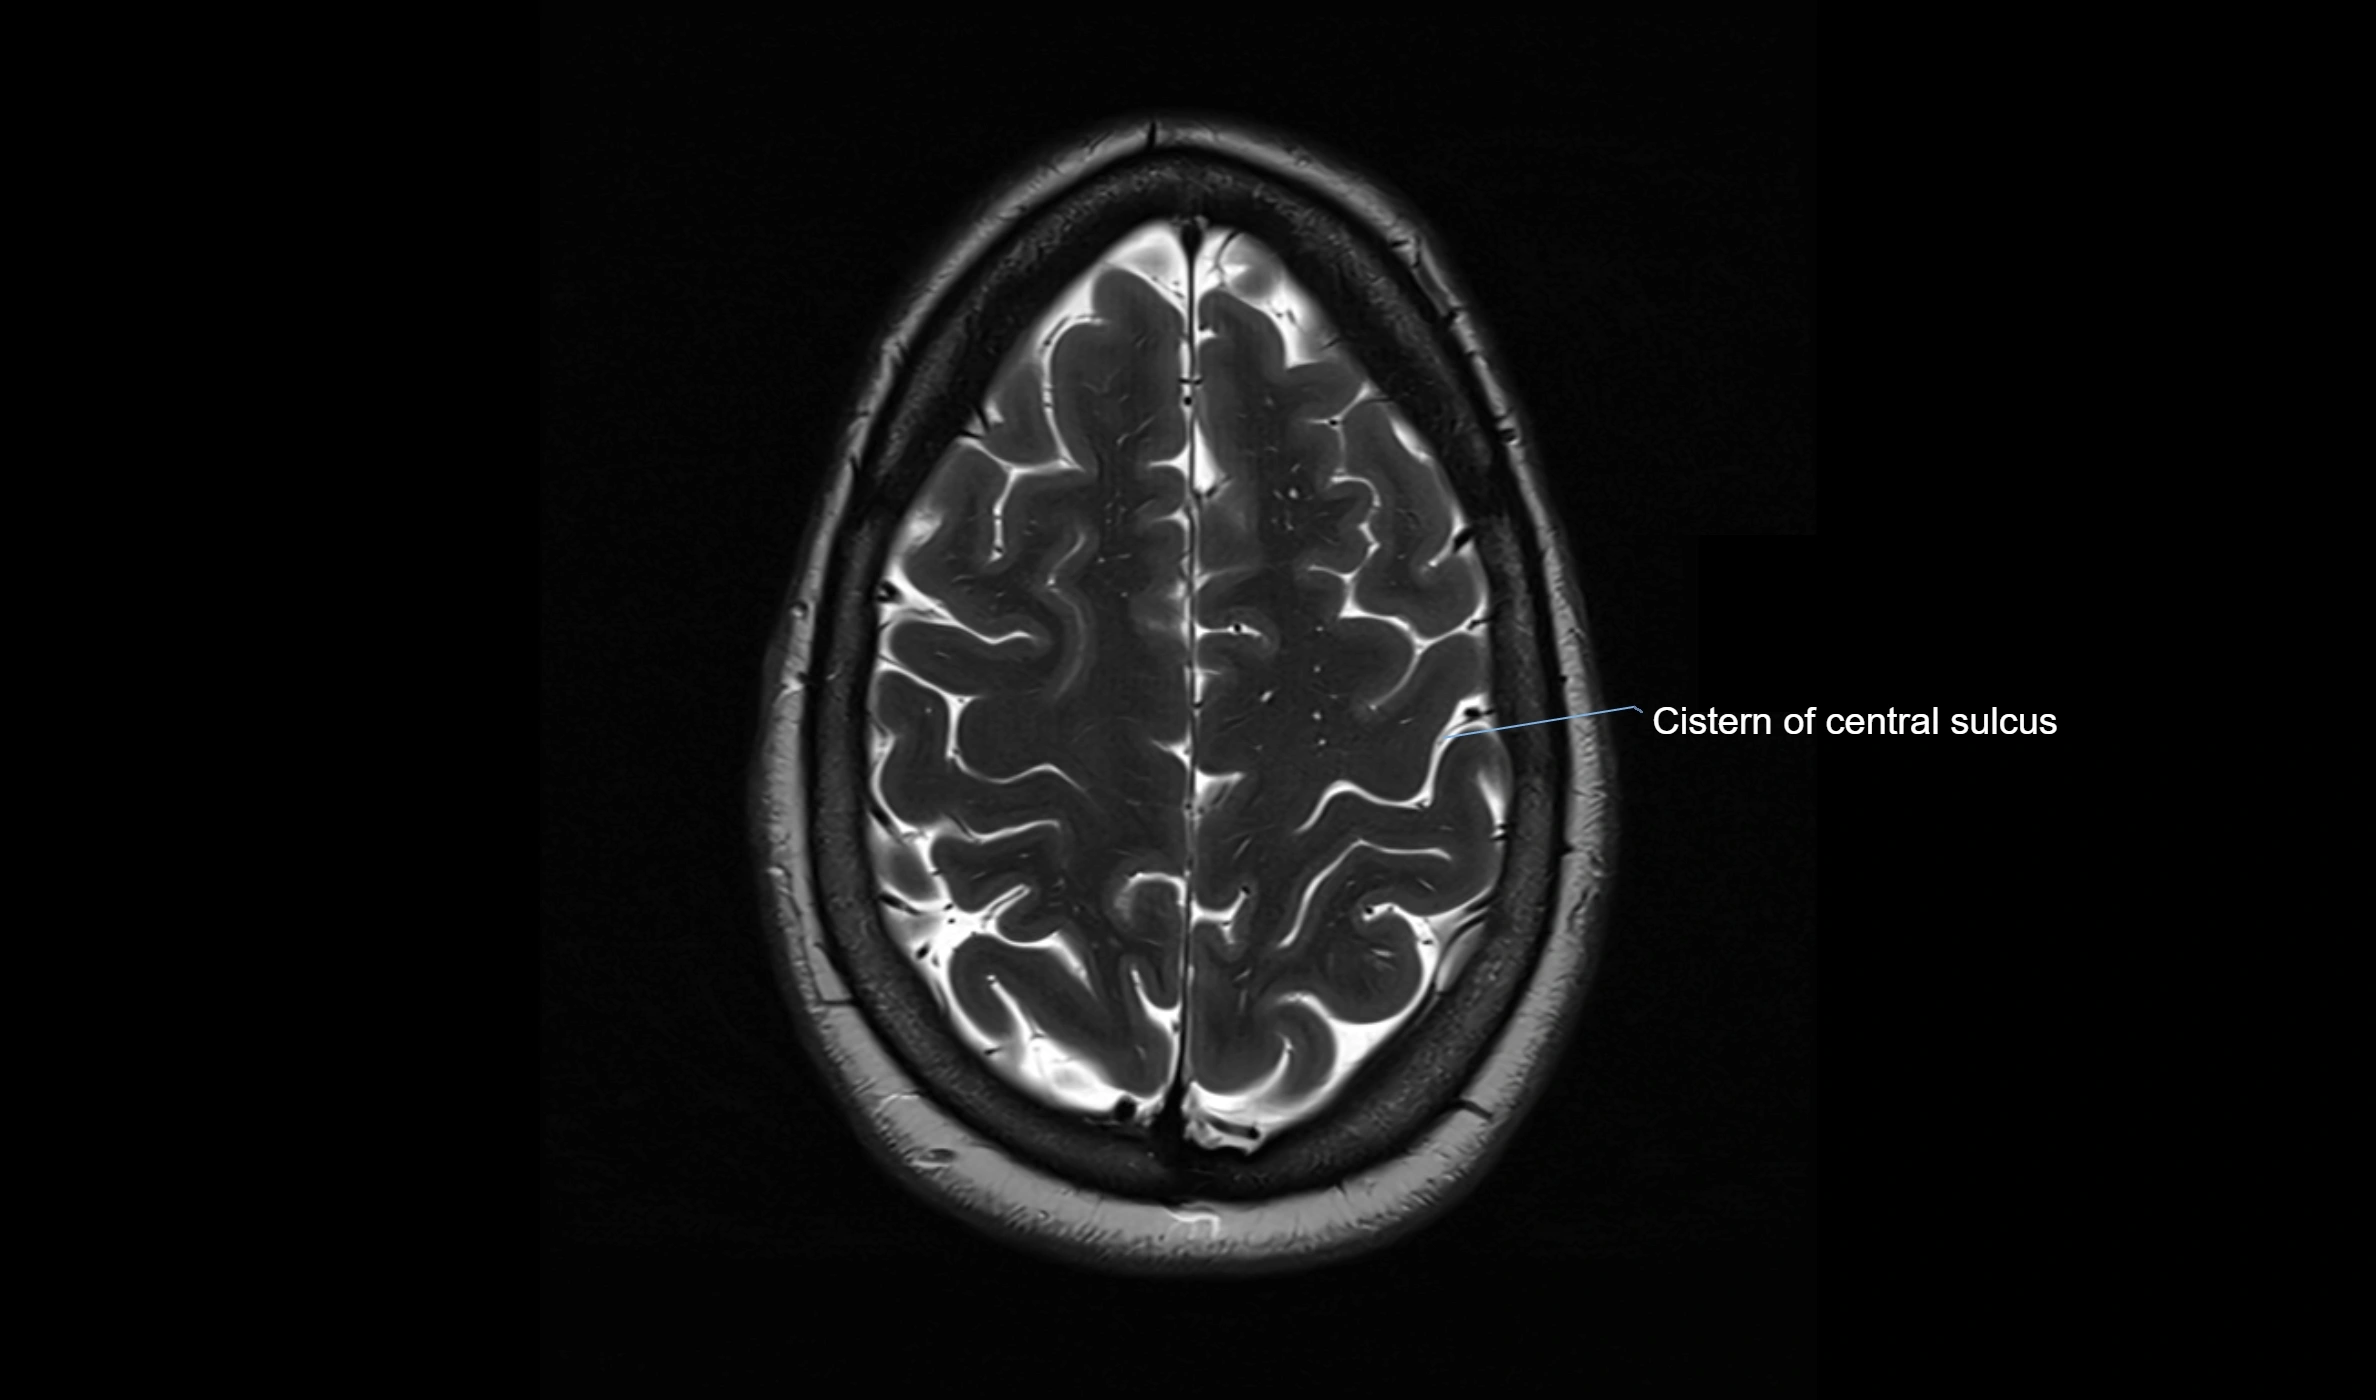

MRI images

image